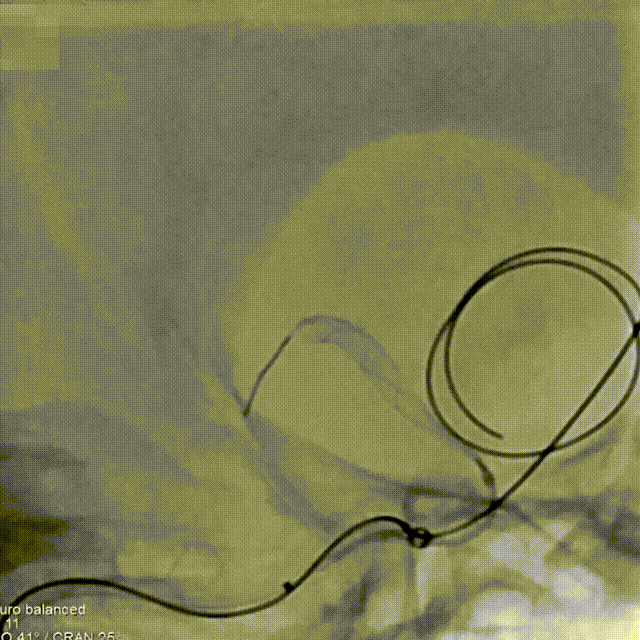

Step3:预埋弹簧圈不解脱,输送Tubridge Plus 4.0mm*30mm支架到位、并缓慢回撤支架张力使支架头端打开呈“V”型,缓慢回撤支架到达预释放位置,并造影确认。

Step4:远端锚定与释放;为使支架在瘤颈口处稳定的释放,远端采用较长的锚定长度。并通过回撤支架导管与轻微推挤支架张力的动态平衡方式,使Tubridge Plus前端50%区域的每个节段与血管壁充分贴合。

Step5:弯段释放;支架远端打开稳固后,采用缓慢推挤支架给张策略进行释放,最终使得支架中后端在弯段处充分打开与贴壁。

Step6:支架按摩;支架整体释放完毕后即刻采用“J”型导丝,由远至近对Tubridge Plus支架的每个节点进行充分按摩,使其保证支架每个节段与血管壁充分贴合。

Step7:持续完成弹簧圈栓塞,评估瘤颈口造影剂滞留程度。

Step8:术后即刻工作位造影,可见瘤颈部位及囊内血流滞留明显,支架打开、贴壁良好。